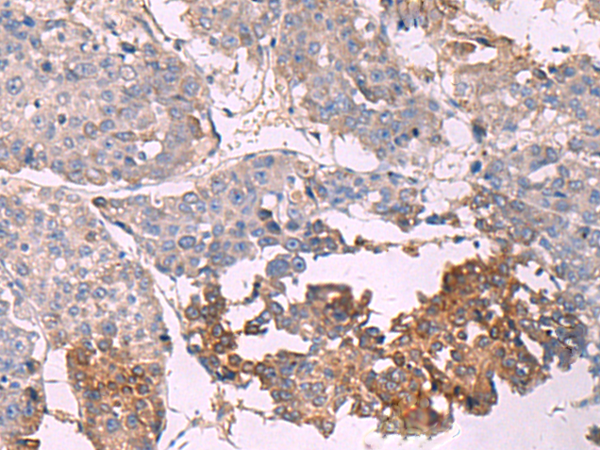

(Immunohistochemistry of paraffin-embedded Human liver cancer tissue using NIPSNAP1 Polyclonal Antibody at dilution of 1:35(×200))